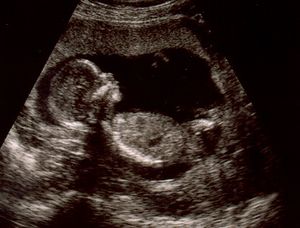

ينتقل الآن مولدك في المستقبل إلي مرحلة مختلفة في النمو حيث يختلف اسمه الآن وينتقل من مجرد حميل إلي جنين كما يسمى في الأغلب. يبدأ الرحم في الاتساع ليشتمل علي منطقة أوسع وأكبر، وينمو الجنين أكثر ويصبح حوالي 2.5 سم طولاً . تحدث تغيرات كثيرة للجنين من عضلات وأعصاب للقيام بوظائفها، تبدأ اليد في التثبت بالمعصم وتبدأ الجفون في تغطية منطقة العين. تظهر أيضاً مع بداية هذا الأسبوع تغيرات جسمانية علي السيدة كالتي تظهر في بداية الحمل حيث يتضخم الثدي بشكل أكبر ويتسع محيط الخصر.